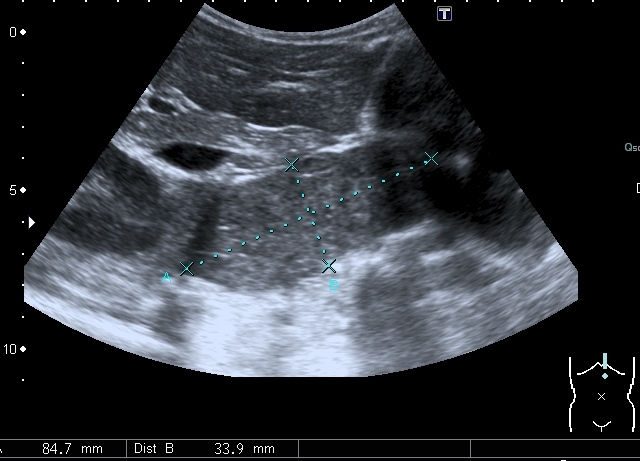

Предлагаю интересные изображения, полученные при сканировании лёгких через межрёберные промежутки и печень у ребёнка 4-х лет с подозрением на пневмонию

Согласен в отношении нижней доли правого лёгкого, изменения в ней похожи на сливную инфильтрацию при пневмонии, хотя носят несколько многоузловой характер. Но то что мы видим со спины в левом лёгком на пневмоническую инфильтрацию не похоже.

Добавляю сканы печени, я думаю они являются хорошей подсказкой о природе изменений в лёгких

Добавляю источник изменений в легких, печени и забрюшинном пространстве

Всё левое подреберье было выполнено опухолевым конгломератом, источником его я предположил левую почку, хотя разобраться , где почка, селезёнка, а тем более надпочечник я не смог.

По сложившейся тактике при обнаружении опухолевых образований мы не занимаемся морфологической верификацией, а отправляем ребёнка в головное учреждение, наверное это правильно - в лечении детских опухолей иногда бывают важны даже часы. Тем не менее , по УЗИ картине больше данных за нефробластому - есть остатки деформированной собирательной системы в области нижнего полюся образования, там же - немного ткани, похожей на нормальную почечную.

ЦДК образований в лёгких не делал, если быть откровенным, порядок находок у этого пациента был следующим: МТС в печени - изменения в нижней доле правого лёгкого - забрюшиное пространство - левая почка - левое лёгкое - правое лёгкое - рентген лёгких. Картина в комплексе была и так ясна, т.е. то, что это MTS сомнений не вызывало. Ну а после патогномоничной рентгеновской картины - вопросов тем более не было.